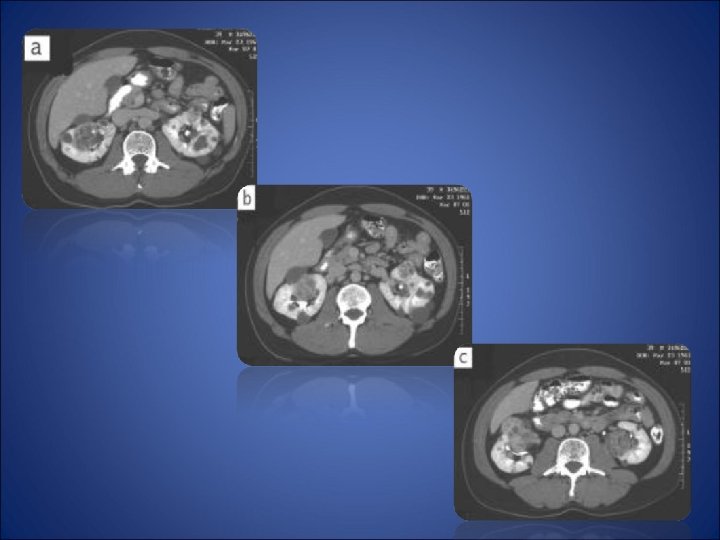

Diagnosis • • • CT scan Ultrasonography MRI Renal arteriography Percutaneous cyst puncture

Surgical Treatment Radical nephrectomy has been the standard of care for localized renal cell carcinoma since the description by Robson. Partial nephrectomy has been used to avoid dialysis in patients with a solitary kidney, compromised renal func tion, or bilateral multifocal (hereditary) tumors. However, performed in patients with small renal tumors (less than 4 cm) has been associated with survival similar to that found after radical nephrectomy.

Partial Nephrectomy Sporadic renal cancer A solitary small renal tumor is ideally suited for partial nephrectomy with an adequate margin. Surface cooling for 10 minutes with ice slush will then provide up to 3 hours safe ischemia. Excision of the renal tumor with a 1 cm margin is performed by the appropriate technique, including wedge resection, transverse or amputation, or segmental renal artery occlusion with resection of the appropriate renal segment. Small polar tumors may be exc ised with local pressure in the absence of renal artery occlusion. Extracorporeal partial nephrectomy with renal autotransplantation is seldom performed now except in the setting of the Jehovah’s witness with multiple or complex tumors. Five- year cancer specific survival after partial nephrectomy has been reported to be 87 to 90%, with a local recurrence in 4 to 6%.

Partial Nephrectomy Nephron sparing surgery (NSS) is an accepted method of treatment for selected renal masses. Long term results for properly selected masses reveal oncologic control comparable to the golden standard, radical nephrectomy. Laparoscopic partial nephrectomy (LPN), has been shown to be technically feasible by several authors including Janetschek, Mc. Dougall, Gill, Rassweiler, and others. The goal of LPN is to maintain the principles of open NSS in order to maintain the excellent oncologic control associated with NSS. The challenge with LPN is attainment of suitable hemostasis. The indications for LPN are fairly straightforward. The patient must be able to tolerate a laparoscopic procedure. The properly selected renal lesion should be less than 4 cm in size and peripheral in nature. Polar lesions are preferable, especially early in the laparoscopic surgeon’s experience with this technique. Renal masses abutting the hilar vessels and central collecting system can be safely resected by the experienced surgeon. Patients with prior renal surgery or history of anyinflammatory conditions of the operative kidney should be avoided.